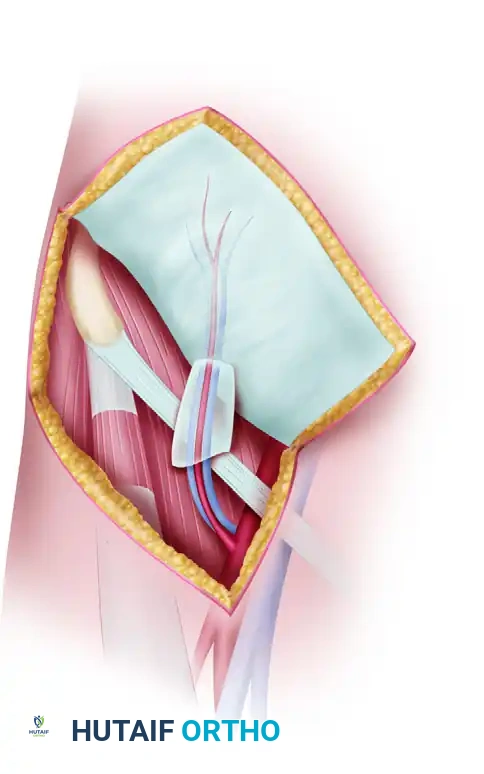

2. Thumb Adduction Release

Releasing the tethered thumb requires meticulous deep dissection, balancing aggressive muscle release with neurovascular preservation.

- Begin by making another incision on the dorsum of the thumb web at the same level as the V-shaped cleft incision.

- Extend this incision distally, parallel with the index split incision, until it reaches the distal edge of the thumb-index web. This creates a vital strip of dorsal skin that remains connected to the index finger and the dorsum of the hand.

- Vascular Preservation: Develop the split flap from the dorsum. Carefully tie off small dorsal veins only when absolutely necessary; do not dissect them off the flap. The viability of this flap is entirely dependent on robust venous drainage.

Surgical Warning: The branches of the median nerve and the radial artery are highly vulnerable during this stage. The radial artery, in particular, must be identified and protected as it dives between the two heads of the first dorsal interosseous muscle.

- Deepen the thumb-index incision to release the dense fibrous bands tethering the two metacarpals.

- Detach the origins of the first dorsal interosseous muscle from the metacarpals.

- Elevate the adductor pollicis muscle and the radial belly of the flexor pollicis brevis from their origins.

- If full thumb abduction is still restricted, carry the dissection down to the capsule of the carpometacarpal (CMC) joint. A dorsal capsulotomy may be required to achieve a fully abducted posture.